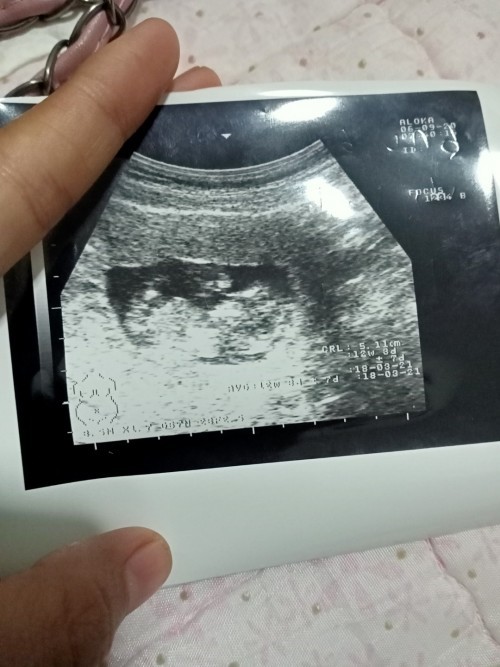

ซาวด์ครั้งแรกท้อง11วีคก้เจอแบบนี้เรยค่ะเสียใจกังวลมากค่ะอีก2อาทิตย์หมอนัดอีกเรายังมีหวังที่จะเจอตัวน้องยุไหมคะสอบถามแม่ๆที่เจอเรื่องแบบนี้หน่อยค่ะขอบคุณสำหรับคำตอบค่ะ😔

11วีคแล้ว น่าจะซาวเจอน้องแล้วนะคะ

ภาพตอน12วีค3วันค่ะ